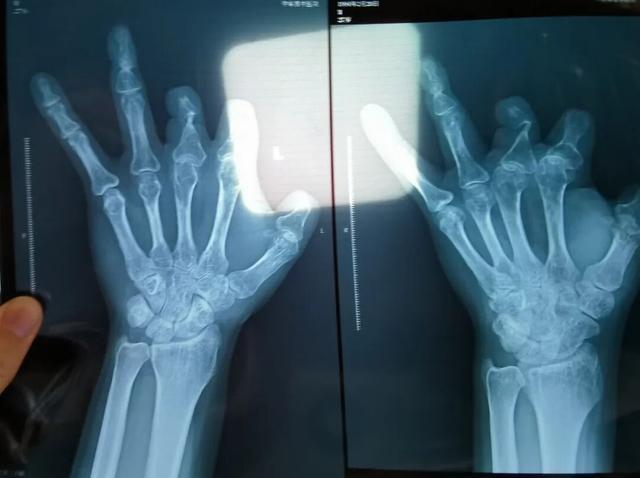

该产品的代理商曾向新京报记者证实,微血管吻合装置为植入型医疗器材,患者拍摄X光片时会有显示。新京报记者获取了一位曾在郑大一附院接受手术、使用了该产品的患者的X光片,其手术部位可见一绿豆大小的光圈。

患者王海森左手拇指关节以上部位被电锯切断,收费单显示术中使用了微血管吻合装置,但X光片中未显示该器械。新京报记者 程亚龙 摄

单价1.68万元,声称在术中植入体内、用于缝合血管的两个环形吻合装置,竟然在王海森的X光片上消失了。

王海森称,他出院约1年后,有人曾找到他说,这个价格昂贵的进口器材,并没有在手术中使用。当时他没有相信,直到2021年12月,经人提醒,王海森在老家开封尉氏县人民医院拍摄了左手X光片,才确认手术部位的确没有微血管吻合装置。2021年12月底,王海森向郑州市公安局二七分局刑侦大队报案。

彭先生称,因为他的手术并不成功,术后他委托律师欲将郑大一附院诉至法庭。在律师的指导下,他到医院拍摄了X光片,偶然发现术中使用的6个吻合装置,都“消失”在了血管内。

2021年12月,患者彭先生拍摄的左手X光片,未见收费单据中列出的微血管吻合装置。新京报记者 程亚龙 摄

装置上带有不锈钢针,不可能被人体吸收,唯一的可能就是“手术时其实没有使用”。尽管之前也有其他人向王海森透露过这一点,但直到看到片子前,他一直都不相信。